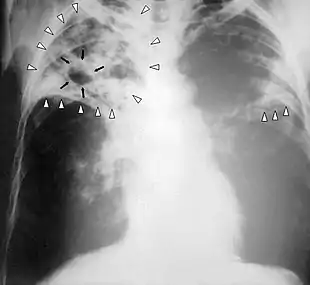

Chest X-ray of a person with advanced tuberculosis: Infection in both lungs is marked by white arrow-heads, and the formation of a cavity is marked by black arrows.

Chest X-ray of a person with advanced tuberculosis: Infection in both lungs is marked by white arrow-heads, and the formation of a cavity is marked by black arrows.